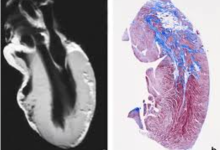

心血管MRI(cardiovascular MRI,CMRI)自20世纪80年代开始逐步应用于临床。近年来,随着MR设备和技术的发展,CMRI以其高时间和空间分辨力、最佳软组织对比度、大视野、无辐射危害、成像参数多、获得信息量大等优势,在心...